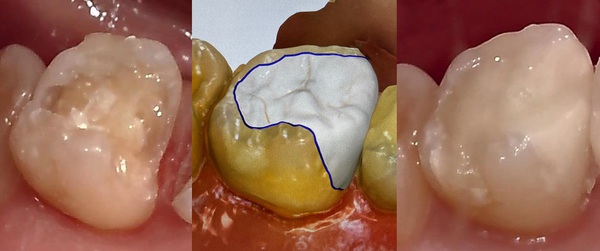

女性Yさん40代 奥歯

セレック(オールセラミック)

詰め物(インレー)

費用 55,000円